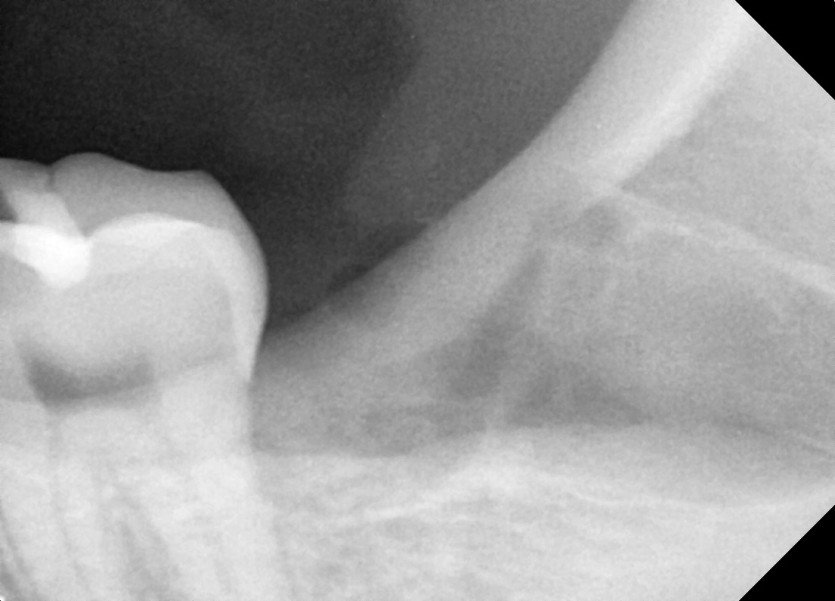

#38 사랑니 발치

구강 외과 전문의가 당일 발치했습니다.